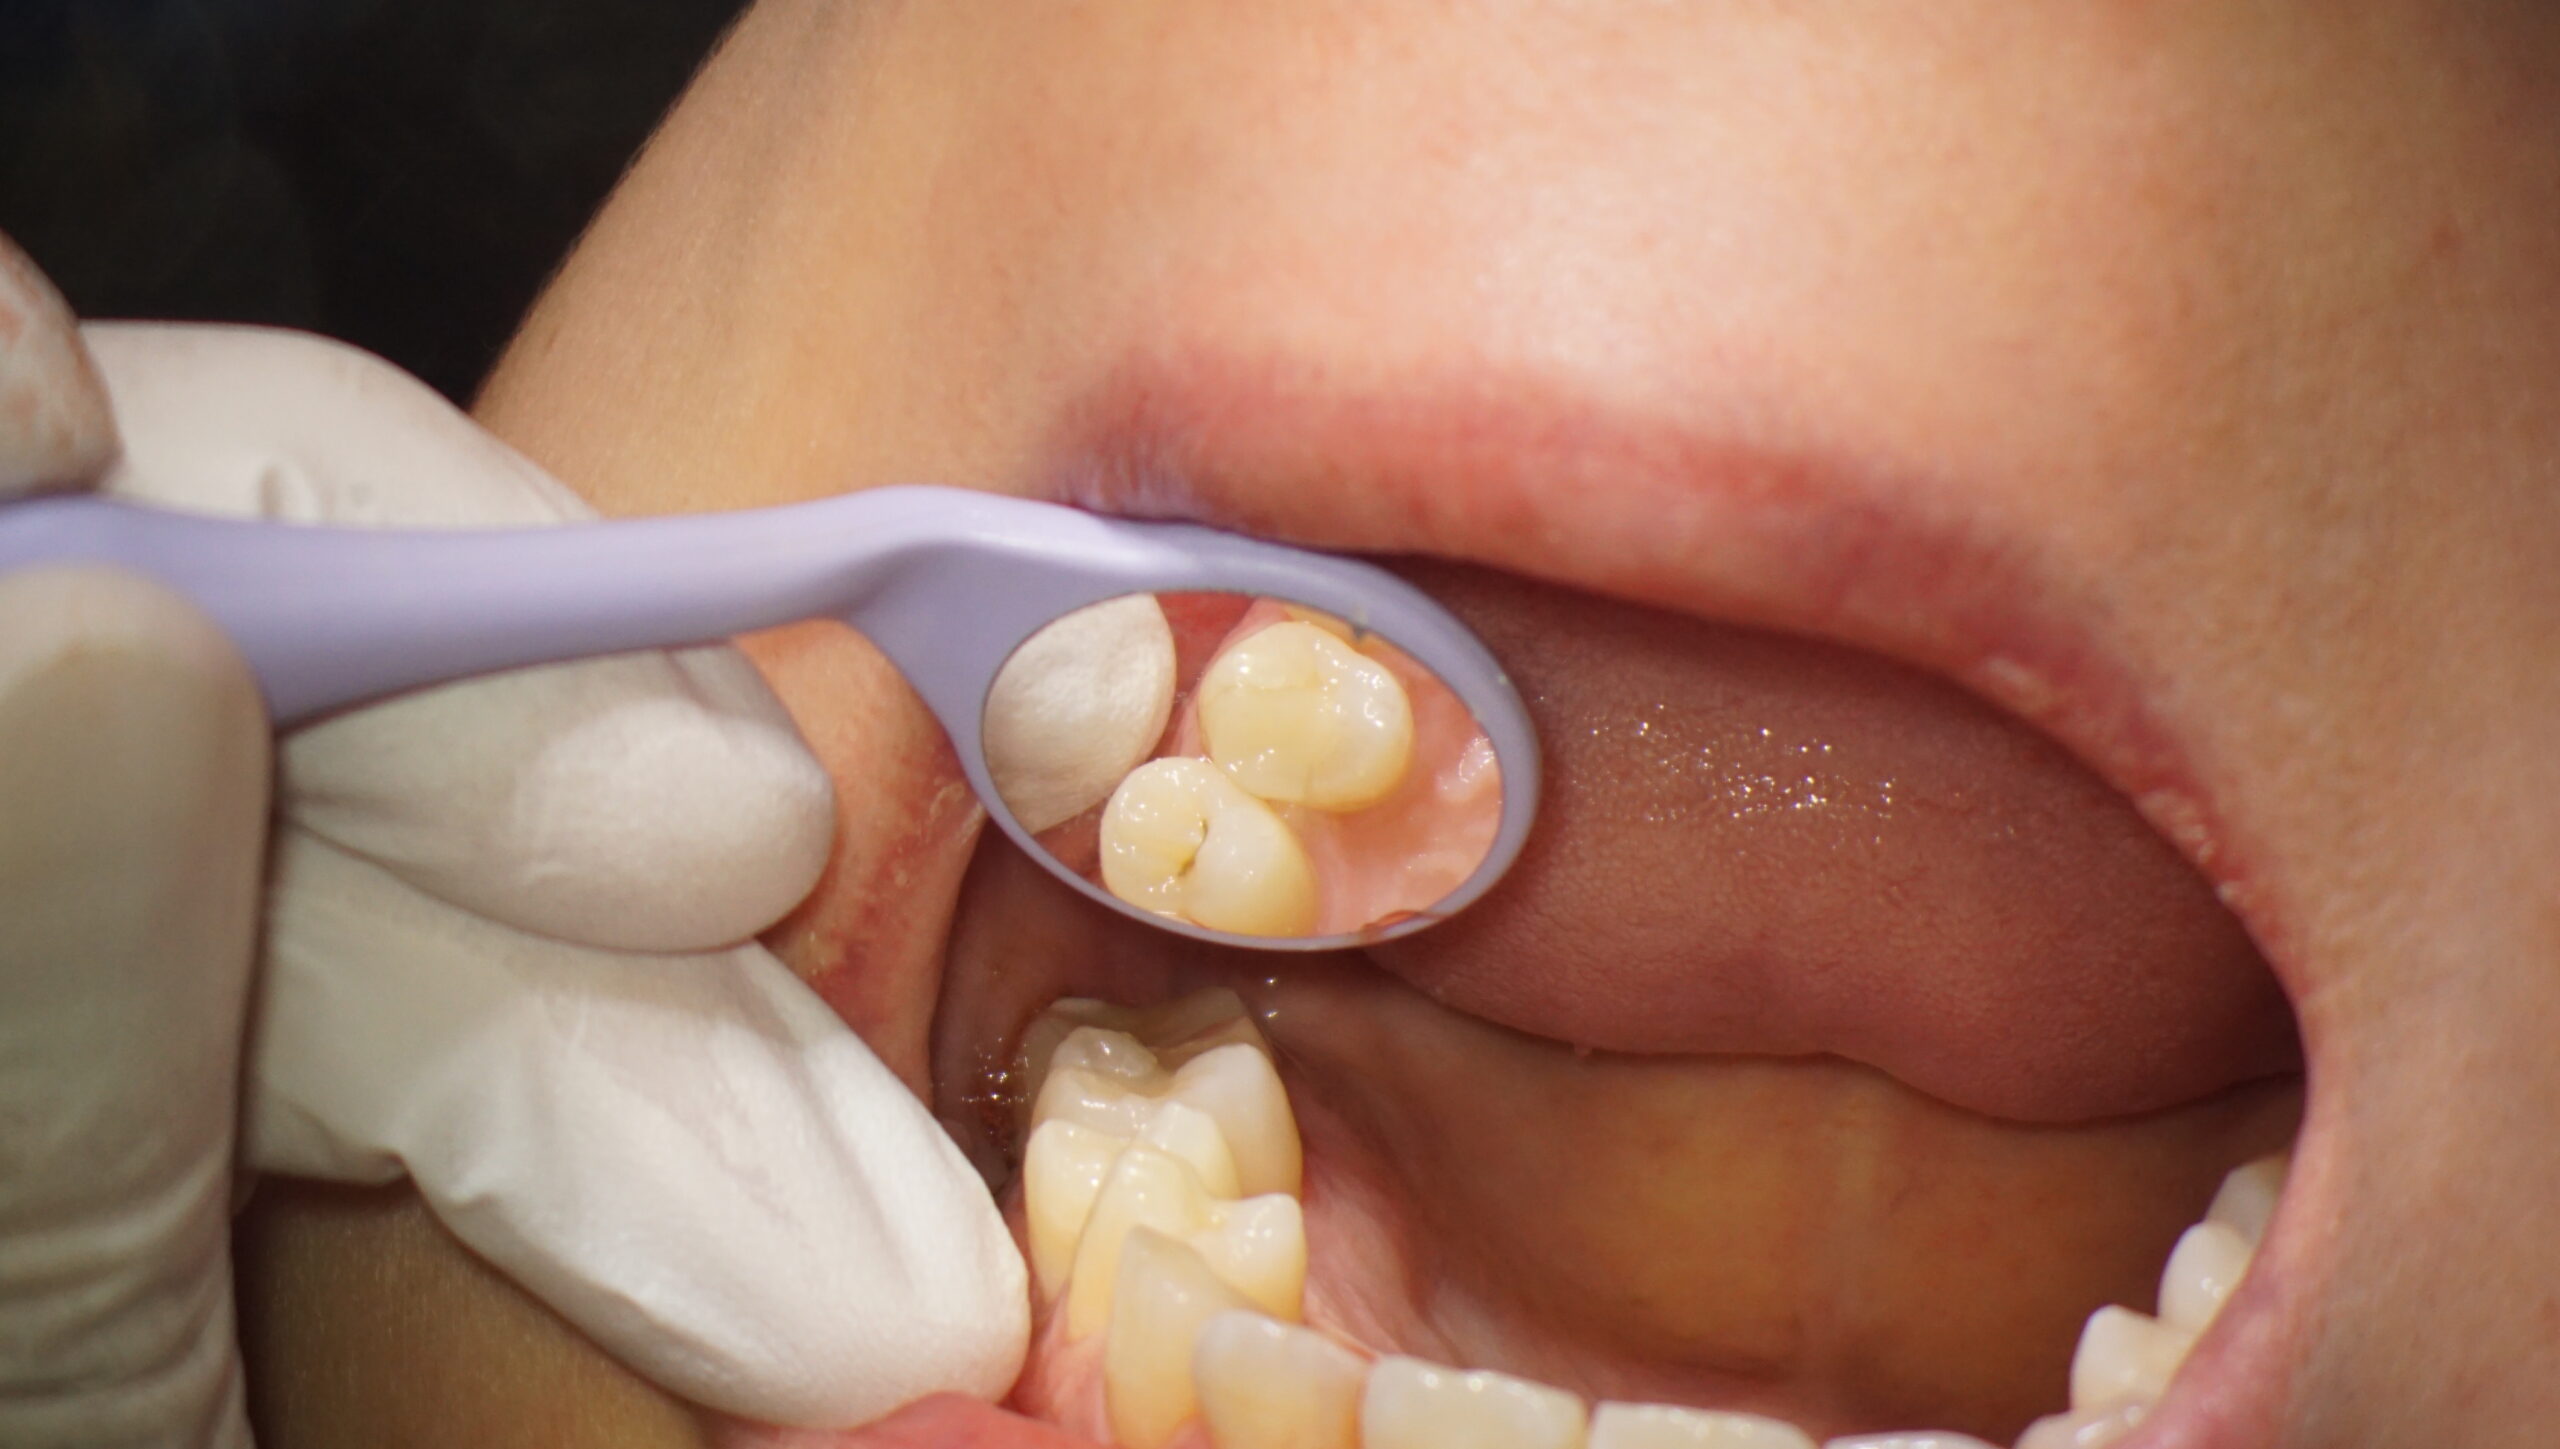

術前の状況です。当院で使用しているマイクロスコープ(グローバルA)に搭載したカメラで撮影したものです。

以前に装着されているインレー(比較的小規模の歯への詰め物です)に小さな虫歯があり、やり直すことになりました。

拡大視野です。歯ぐきと歯がしっかり分離できているのがわかります。

非常に処置が行いやすく、よりクオリティの高い状態を維持することができます。

マイクロスコープを用いて形成を行うとき、ミラーの中の画像と、直接ドリルを見るのと、視点は二つを交互に移動させます。

マイクロスコープの弱点は視界の立体感の乏しさです。

理由は忘れましたが(笑)、ルーペや裸眼に比べて立体感を捉えにくく、視点をうまく移動させて立体の情報を補完します。

しかし、圧倒的倍率と視点の安定さで、形成処置においては大きな大きな助けになります。

形成が終了しました。